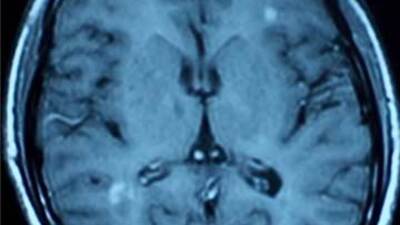

Uluslararası bir ekip tarafından yapılan ve sonuçları Nature dergisinde yayımlanan araştırma, MS hastalığında insan hücreleriyle bağışıklık sistemi faktörleri arasında bağ bulunduğunu gösterdi.

15 farklı ülkeden, 9 bin 700'ün üzerinde MS hastasının verilerini yaklaşık 17 bin 400 sağlıklı insanın bilgileriyle kıyaslayan araştırmacılar, MS ile ilgili daha önce belirlenen 20 genin yanı sıra 29 yeni gen varyasyonu tespit etti. Bu genler MS hastalığına yakalanma riskinde rol oynuyor.

Yeni tespit edilen genler, hücresel bağışıklıkta önemli rol oynayan T-lenfositlerine işaret ediyor. Yeni genlerin büyük bölümü, başka bağışıklık sistemi hastalıklarında da rol oynuyor.

Araştırma, MS hastalığında D-vitamini metabolizmasının rol oynadığı tezini de doğruluyor, çünkü bulunan genlerin ikisi bu metabolizmayla ilgili.